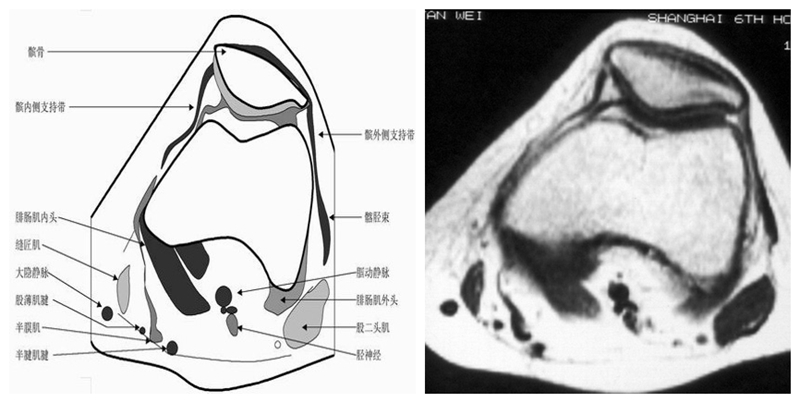

膝关节横断面MRI解剖

三维影像首选的方位,便于与CT比较,可准确地展现髌骨内外侧关节面。

横断面解剖第一层